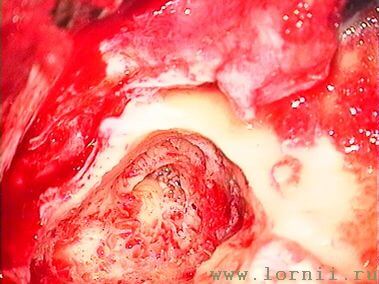

У пациентов с аномалией развития уха и после радикальной операции катушка импланта была установлена в круглое окно (рис. 13, 15, 16). Для этого крепление катушки подворачивали (рис. 14). Далее укладывали фасцию височной мышцы в нишу окна улитки (рис. 15), затем на фасцию устанавливали катушку импланта и подворачивали края фасции. Фиксация конструкции обеспечивалась полоской аутохряща из ушной раковины пациентки (рис. 16).